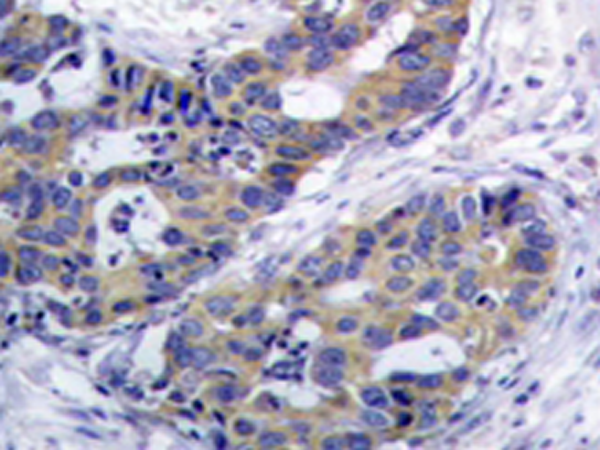

IHC positive control:

Human breast carcinoma tissue